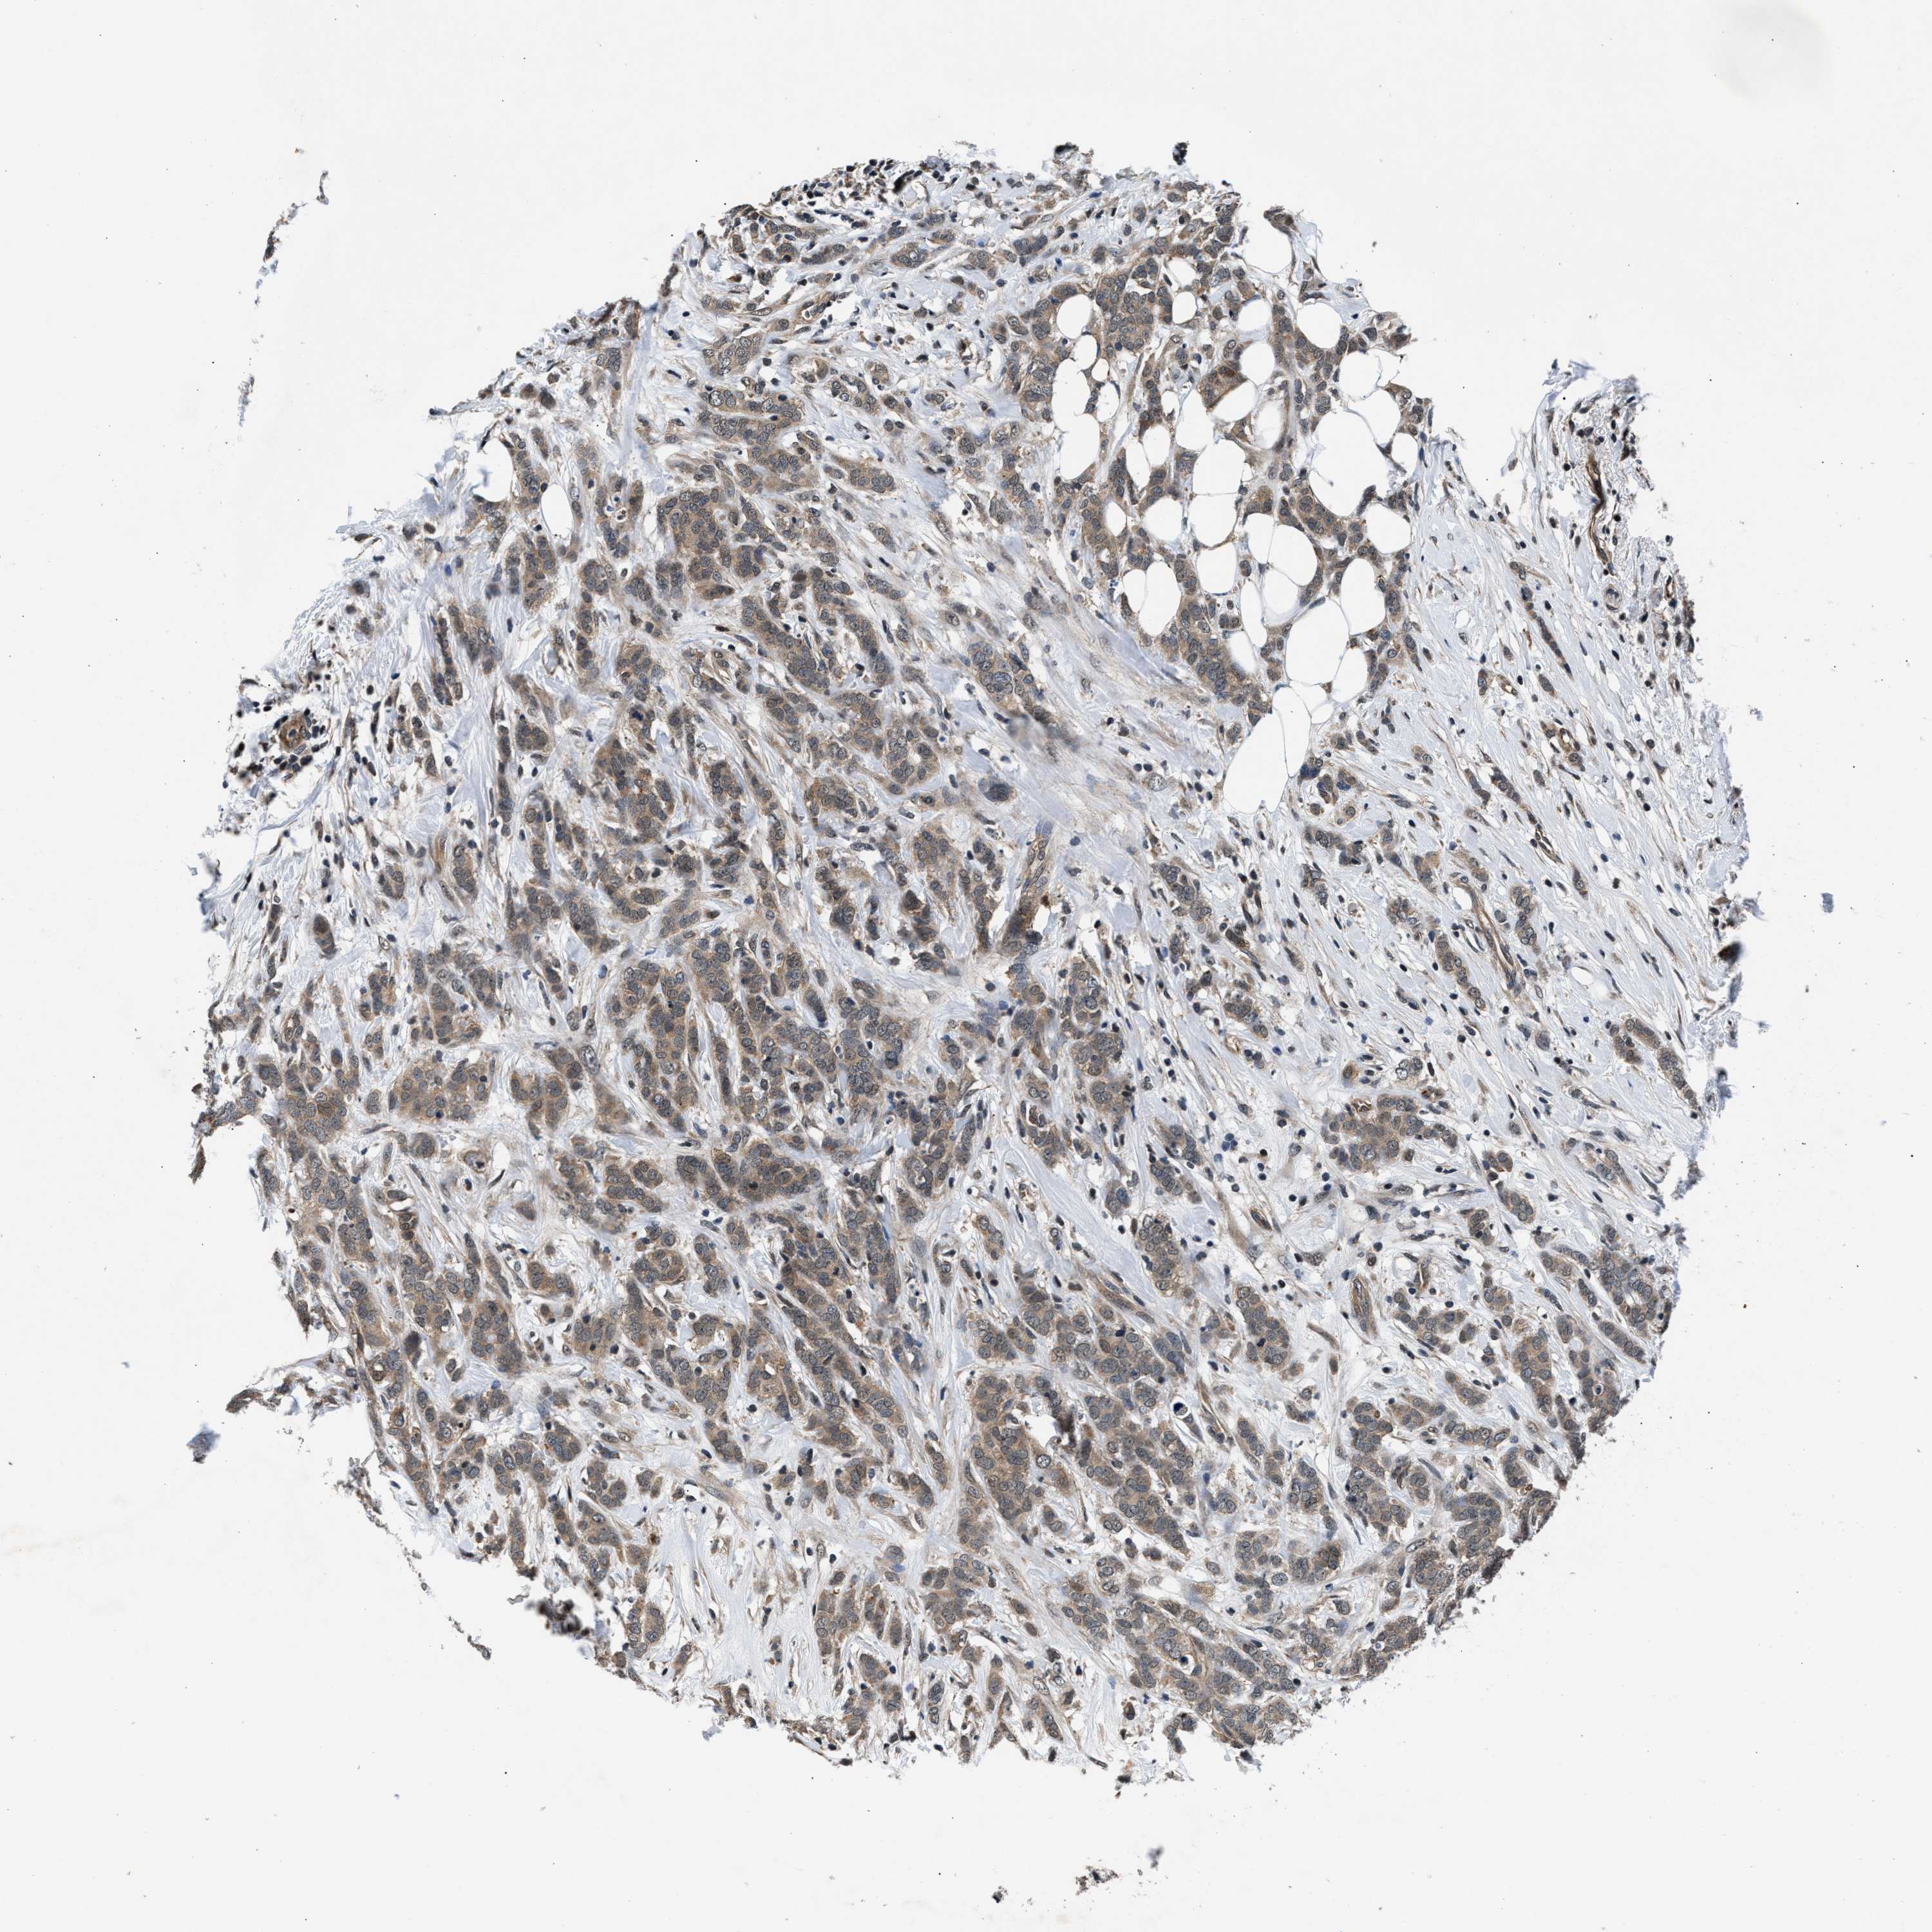

BRCA TCGA BRCA VALIDATION PROTEIN EXPRESSION